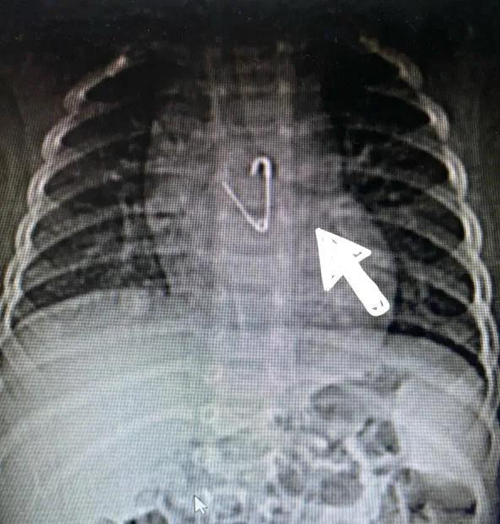

10月4日,剛剛8個(gè)月的小鵬鵬(化名)在家玩耍時(shí),不小心吞下一枚別針。心驚膽戰(zhàn)的一家人從平度趕到青島婦兒醫(yī)院就診,接診醫(yī)生迅速為小鵬鵬安排相關(guān)檢查,CT結(jié)果顯示:別針尖端已打開,誤吞的別針?biāo)幬恢梅浅措U(xiǎn),位于食管約胸椎5-7水平處。

此時(shí)正值國慶節(jié)假期,內(nèi)鏡中心主任任悅義和消化科醫(yī)生王瑩瑩第一時(shí)間趕到醫(yī)院。根據(jù)X線攝片顯示異物位置及兒童消化道結(jié)構(gòu)特點(diǎn),消化科和內(nèi)鏡中心團(tuán)隊(duì)制定了多種治療方案。在氣管插管全身麻醉后,消化科團(tuán)隊(duì)為患兒實(shí)施胃鏡檢查。醫(yī)生操作小兒細(xì)胃鏡進(jìn)入食管后,未發(fā)現(xiàn)有異物,繼續(xù)進(jìn)鏡發(fā)現(xiàn)別針已經(jīng)掉入胃內(nèi)幽門口附近,尖端扎入幽門口,萬幸未進(jìn)入腸道,孩子的食管粘膜及胃內(nèi)無明顯損傷及穿孔。根據(jù)術(shù)前制定的預(yù)案,消化科醫(yī)生先用異物鉗把別針“拖”到胃內(nèi),然后加上透明帽,防止損傷胃和食道粘膜,最后通過胃鏡把別針成功取出,手術(shù)過程不到5分鐘,寶寶轉(zhuǎn)危為安。